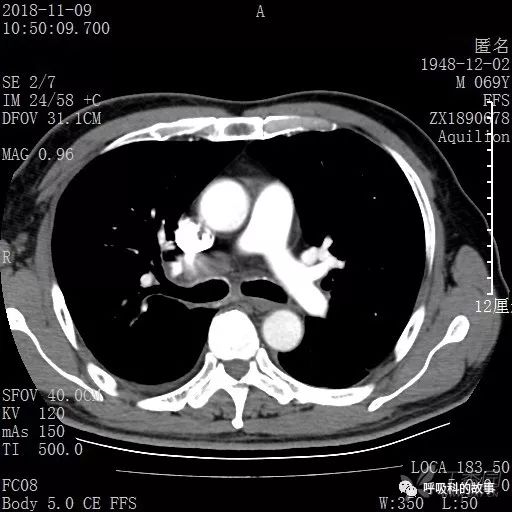

胸部增强CT示右肺门占位伴远端阻塞性肺炎,纵膈、右肺门、右侧颈根部、右侧腋下及肝门部肿大淋巴结。两侧胸腔少量积液。

纵隔窗的增强CT

肺窗CT